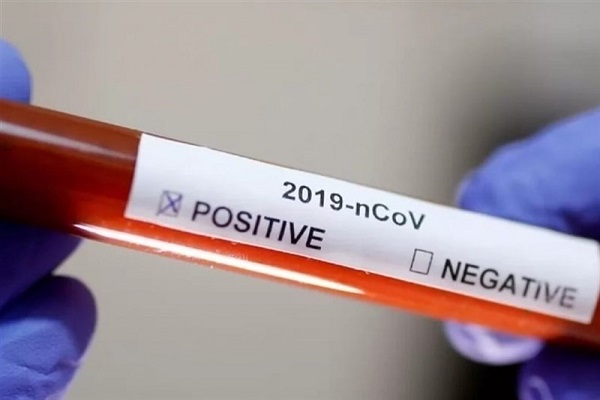

انجام تست رایگان کرونا در مسجد «سنآنتونیو» تگزاس

یک مرکز آموزشی مرتبط با مسلمانان در آمریکا مسجد «سنآنتونیو» تگزاس را بهعنوان پایگاهی برای انجام تست رایگان کرونا اختصاص داده است.

شناسایی 1869 مورد ابتلای جدید به کرونا / 14 استان فوتی نداشتند

سخنگوی وزارت بهداشت از شناسایی یک هزار و ۸۶۹ بیمار جدید مبتلا به کووید ۱۹ در کشور خبر داد و گفت: با احتساب این موارد جدید، تعداد کل مبتلایان به این بیماری به ۱۳۳هزار و ۵۲۱ نفر رسید.

تعداد مبتلایان به كرونا در فارس به 3000 نفر نزدیك میشود

معاون بهداشت دانشگاه علوم پزشكی شیراز از شناسایی 135 بیمار جدید مبتلا به کروناویروس و افزایش تعداد مبتلایان به این ویروس به 2 هزار و 959 نفر در فارس خبر داد.

تعرفه آزمایشگاههای خصوصی کرونا / معتبر نبودن تستهای سریع کووید19

مدیرکلآزمایشگاههای مرجع سازمان غذا و دارو، تعرفه آزمایشگاههای خصوصی برای تست کرونا را اعلام کرد و گفت: کیتهای تشخیص سریع ارزشی برای بیماریابی ندارند.

نسبت گزارشهای علمی کرونا با آمارهای وزارت بهداشت

سخنگوی وزارت بهداشت با بیان اینکه آمارهای منتشر شده در همه کشورها آمارهای قطعی است، گفت: ممکن است این آمارها با گزارشهای علمی همخوانی نداشته باشد و این ناهمخوانی به این دلیل است که واقعیت این بیماری نیاز به مطالعات بیشتر دارد.

مدلسازی صحیحی از کرونا نمیتوان ارائه داد

معاون وزیر بهداشت با رد دو ارزیابی اپیدمیولوژیک در رابطه با تعداد ابتلا به ویروس کرونا و مرگ و میر ناشی از آن، گفت: این ویروس چنان بیحساب و کتاب است که مدلسازی صحیحی از آن نمیتوان ارائه داد.